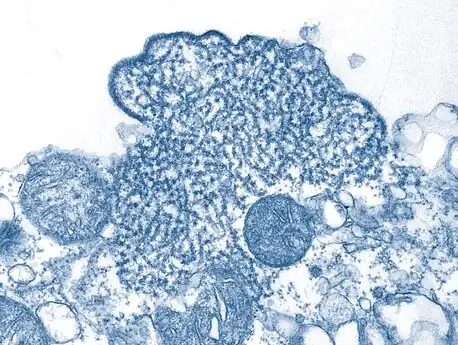

| False-color electron micrograph showing a Nipah virus particle (purple) by an infected Vero cell (brown) | |

Transmission electron micrograph of mature extracellular Nipah Virus particles (yellow) near the periphery of an infected VERO cell